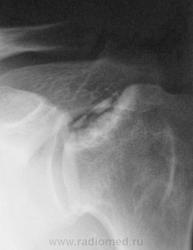

Пол пациента: Мужской пол Тип патологии: Другое Область исследования: Скелетно-мышечная система Методы исследования: Rg Мужчина пожилого возраста обратился с жалобами на боль при движении левой рукой, особенно при отведении её в сторону и вверх. https://radiomed.ru/sites/default/files/styles/case_slider_image/public/user/12/01.1..sl272871.jpg?itok=oY80RVfp https://radiomed.ru/sites/default/files/styles/case_slider_image/public/user/12/02.2..sl272871-3a.jpg?itok=myiw2wOv ID:5598 Ср, 18/08/2010 - 21:18 #1 Катенёв Валенти... Не на сайте Был на сайте: 7 лет 5 месяцев назад Зарегистрирован: 22.03.2008 - 22:15 Публикации: 54876 Здравствуйте Игорь Артурович! Интересный случай представлен Вами. Приложения: Ср, 18/08/2010 - 21:20 #2 Катенёв Валенти... Не на сайте Был на сайте: 7 лет 5 месяцев назад Зарегистрирован: 22.03.2008 - 22:15 Публикации: 54876 Продолжение. Приложения: Ср, 18/08/2010 - 21:20 #3 Глазков Игорь А... Не на сайте Был на сайте: 1 год 2 месяцев назад Зарегистрирован: 19.12.2008 - 20:41 Публикации: 1597 что здесь не только банальный артроз, но больше похоже на сирингомиелию? Прийди к Себе Ср, 18/08/2010 - 21:37 #4 Almo Не на сайте Был на сайте: 3 недели 19 часов назад Зарегистрирован: 28.09.2008 - 18:50 Публикации: 8302 Артроз есть. Сирингомиелия?( должны быть симптомы выпадения темературной чувствителности на руке) Я бы, предложил версию асептического некроза головаки плеча. Ср, 18/08/2010 - 21:40 #5 Глазков Игорь А... Не на сайте Был на сайте: 1 год 2 месяцев назад Зарегистрирован: 19.12.2008 - 20:41 Публикации: 1597 за высказанное мнение. Прийди к Себе Чт, 19/08/2010 - 06:54 #6 Анатолий Владим... Не на сайте Был на сайте: 8 лет 3 месяцев назад Зарегистрирован: 16.10.2009 - 21:16 Публикации: 1941 Согласен с мнением Almo, считаю, что здесь - асептический некроз. Чт, 19/08/2010 - 08:12 #7 Широков.Евгений. Не на сайте Был на сайте: 11 лет 8 месяцев назад Зарегистрирован: 31.08.2008 - 14:29 Публикации: 77 Отдаю свой голос за асептический некроз. Чт, 19/08/2010 - 09:33 #8 Грицько Виталий Не на сайте Был на сайте: 9 лет 4 месяцев назад Зарегистрирован: 05.01.2010 - 14:06 Публикации: 1058 Опоздал на все обсуждения:( согласен с асептическим некрозом. Чт, 19/08/2010 - 12:32 #9 Катенёв Валенти... Не на сайте Был на сайте: 7 лет 5 месяцев назад Зарегистрирован: 22.03.2008 - 22:15 Публикации: 54876 Надо признать, что наблюдение, представленное Вами, уважаемый Игорь Артурович, довольно редкое и займет достойное место в наборе "Асептический некроз" Чт, 19/08/2010 - 16:12 #10 Helios Не на сайте Был на сайте: 1 год 2 недели назад Зарегистрирован: 06.08.2010 - 15:16 Публикации: 4417 Голосую за асептический некроз. Чт, 19/08/2010 - 17:03 #11 lupan Не на сайте Был на сайте: 7 лет 3 месяцев назад Зарегистрирован: 07.01.2010 - 17:17 Публикации: 1406 А есть название по автору? Великое преймущество врача заключается в том, что он не обязан следовать собственным советам. ( А. Кристи) Чт, 19/08/2010 - 17:36 #12 Анатолий Владим... Не на сайте Был на сайте: 8 лет 3 месяцев назад Зарегистрирован: 16.10.2009 - 21:16 Публикации: 1941 Тут большой труд Валентина Львовича: http://www.radiomed.ru/forum/osteohondropatii-nabor-izobrazheniy-0 Болезнь Хасса... Чт, 19/08/2010 - 19:26 #13 Катенёв Валенти... Не на сайте Был на сайте: 7 лет 5 месяцев назад Зарегистрирован: 22.03.2008 - 22:15 Публикации: 54876 Все произошло на "ровном месте". Приложения: Чт, 19/08/2010 - 19:33 #14 Vikkur Не на сайте Был на сайте: 5 лет 3 недели назад Зарегистрирован: 24.09.2009 - 14:34 Публикации: 1749 Передний вывих? Виктор. Чт, 19/08/2010 - 20:59 #15 Almo Не на сайте Был на сайте: 3 недели 19 часов назад Зарегистрирован: 28.09.2008 - 18:50 Публикации: 8302 Можно предоложить, привычный вывих плеча( с учётом анамнеза заболевания конечно, а не скиологической картины). Пт, 20/08/2010 - 08:29 #16 lupan Не на сайте Был на сайте: 7 лет 3 месяцев назад Зарегистрирован: 07.01.2010 - 17:17 Публикации: 1406 Вывих вполне м.б. привычным, судя по величине и форме суставного конца лопатки. Великое преймущество врача заключается в том, что он не обязан следовать собственным советам. ( А. Кристи)

А есть название по автору?

Великое преймущество врача заключается в том, что он не обязан следовать собственным советам. ( А. Кристи)

Тут большой труд Валентина Львовича:

Болезнь Хасса...

Все произошло на "ровном месте".

Передний вывих?

Можно предоложить, привычный вывих плеча( с учётом анамнеза заболевания конечно, а не скиологической картины).

Вывих вполне м.б. привычным, судя по величине и форме суставного конца лопатки.